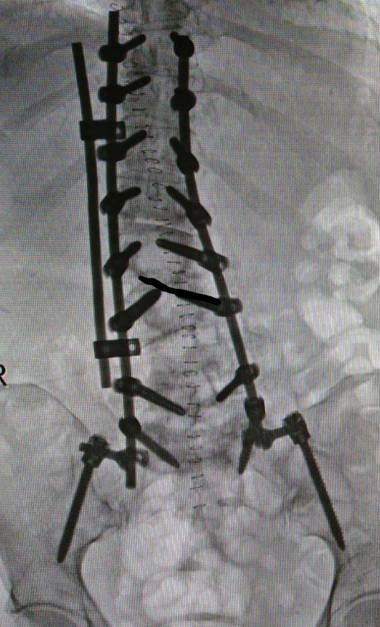

Fusiones cortas. Entendemos por fusión corta a aquella que se realiza dentro de las vértebras afectadas por la escoliosis. Para fusionar una o varias vértebras utilizaremos barras y tornillos. Las fusiones cortas son útiles para solventar síntomas neurológicos y dolor lumbar pero no corrigen la escoliosis. Las fusiones cortas se utilizan cuando hay que hacer una descompresión amplia o en los casos de que la escoliosis tenga vértebras inestables (espondilolistesis y desplazamientos laterales. Para poder hacer una fusión corta es muy importante que tengamos una escoliosis equilibrada, si no es así es muy probable que el resultado de la cirugía no sea el deseado.

Fusiones amplias. Las fusiones amplias se reservan para los casos más extremos y cuando la escoliosis esta desequilibrada. En estos casos trataremos de corregir la forma de la escoliosis y tratar de darle una forma a la columna para recuperar el equilibrio. Se trata de cirugía muy agresiva y que presentan complicaciones en el 30-50% de las ocasiones. Hay estudios que dicen que al menos en 30% de los pacientes va a necesitar una cirugía para corregir complicaciones.

La cirugía de corrección de escoliosis del adulto consiste en realizar grandes incisiones, en las que ponemos muchos tornillos, además realizamos cortes en las vértebras denominados osteotomías para tratar de modificar la forma de la columna.